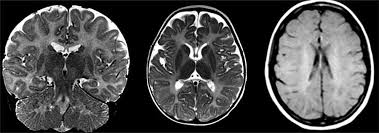

- Brain MRI showing abnormal myelin formation